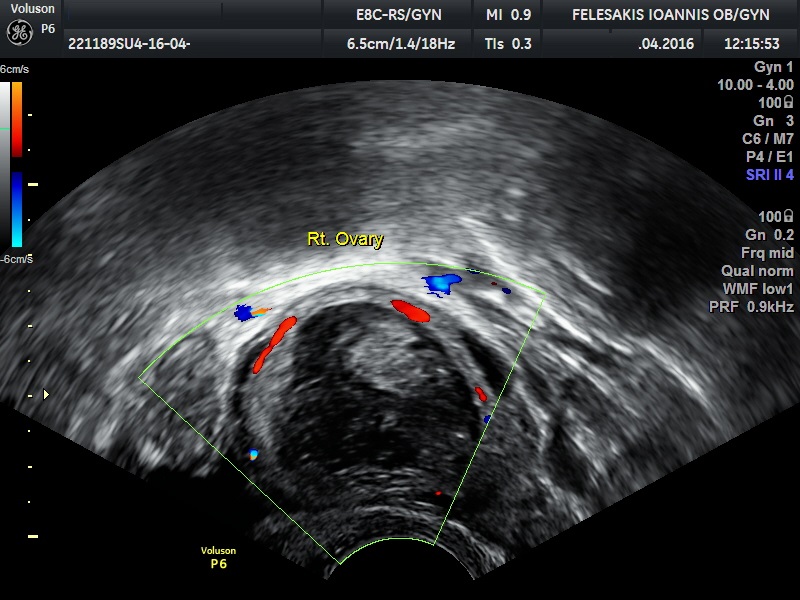

√ Παρακολούθηση ωορρηξίας σε φυσιολογικό κύκλο και κατόπιν ωοθηκικής διέγερσης

√ Πολυκυστικές ωοθήκες